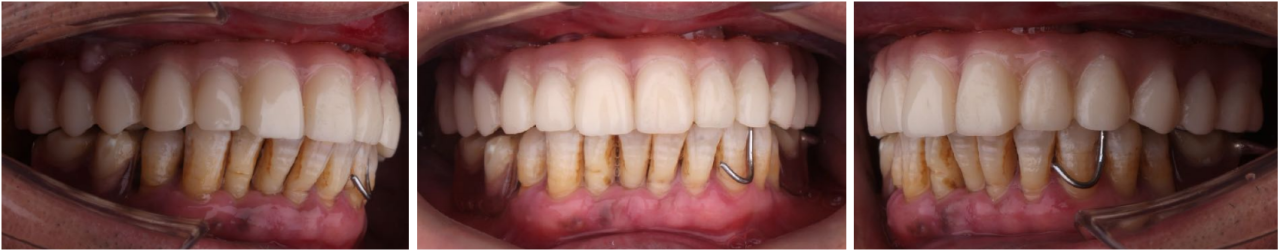

永久修复3年随访:

上下颌边缘骨稳定,零骨吸收

通过修复后口内照观察到,美学效果良好,无基台种植体配合性能相关的周围炎。通过医学影像观察到,修复三年后种植体周围无骨吸收,患者非常满意。